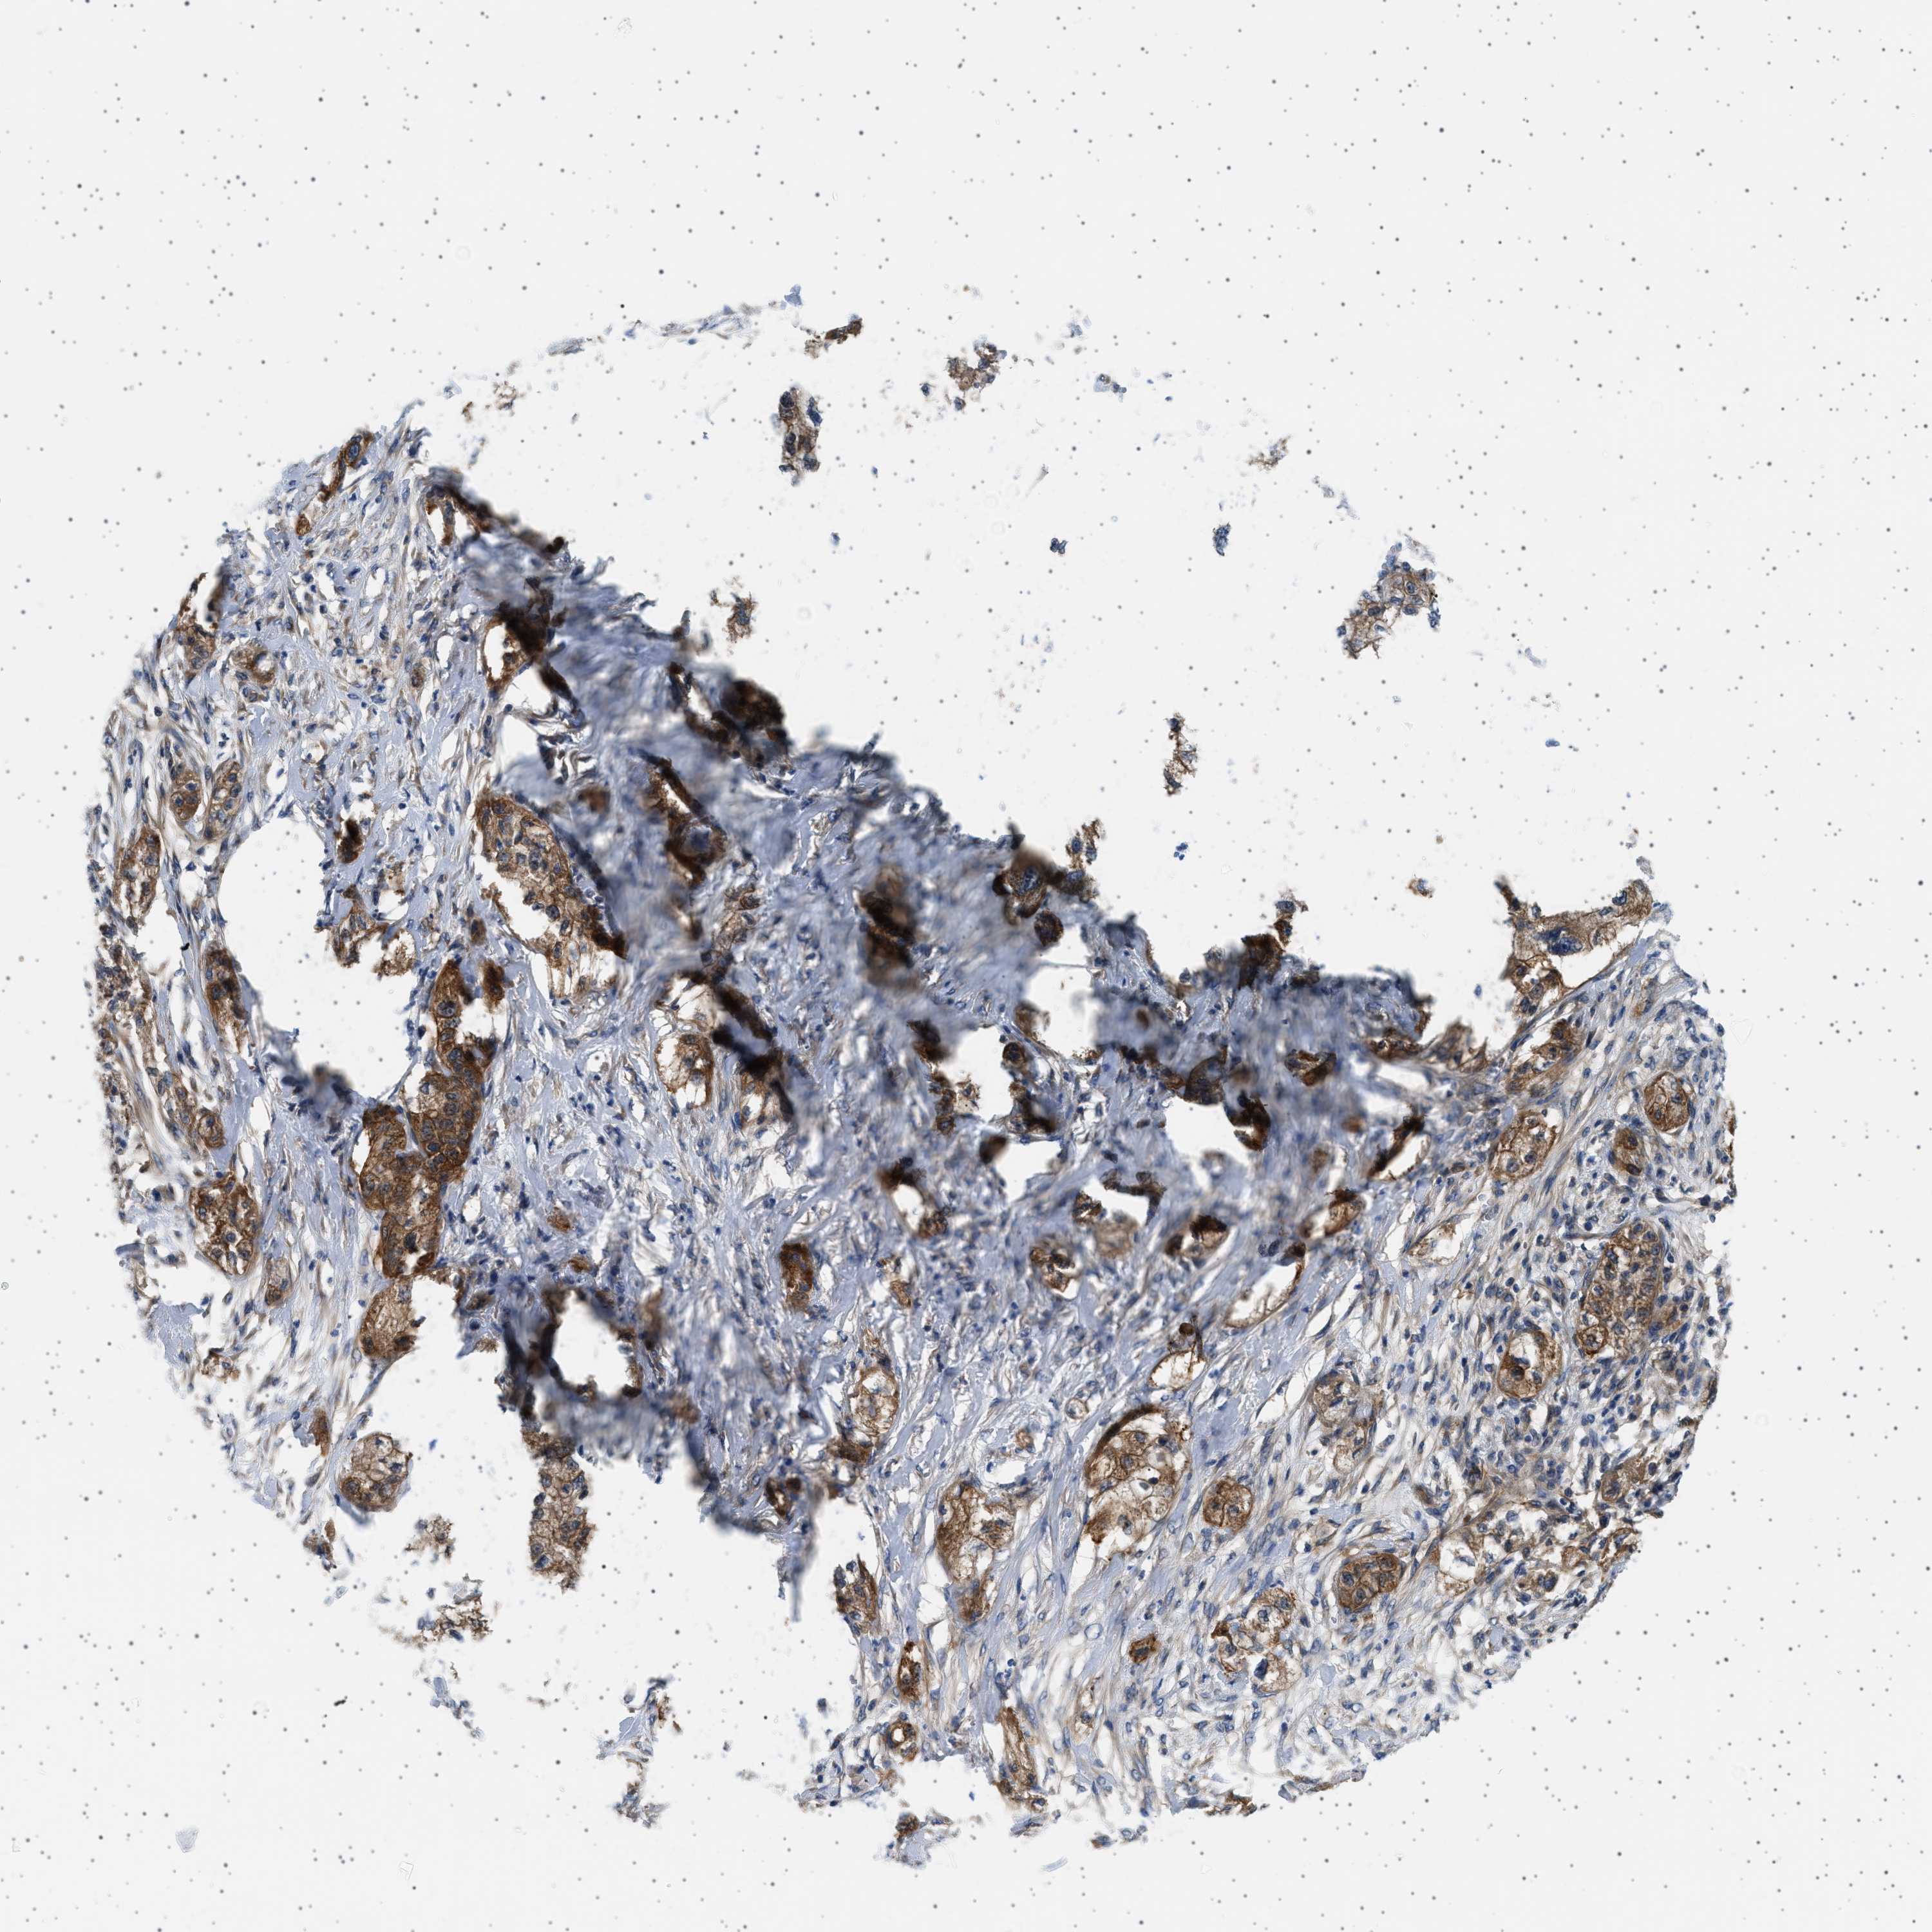

PANCREATIC CANCER - Protein expressioni

A mouse-over function shows sample information and annotation data. Click on an image to view it in a full screen mode. Samples can be filtered based on level of antibody staining by selecting one or several of the following categories: high, medium, low and not detected. The assay and annotation is described here.

Note that samples used for immunohistochemistry by the Human Protein Atlas do not correspond to samples in the TCGA dataset.

Antibody stainingi

Antibody staining in the annotated cell types in the current human tissue is reported as not detected, low, medium, or high, based on conventional immunohistochemistry profiling in selected tissues. This score is based on the combination of the staining intensity and fraction of stained cells.

Each image is clickable and will lead to virtual microscopy that enables deeper exploration of all samples and also displays staining intensity scores, fraction scores and subcellular localization as well as patient and tissue information for each sample.

Antibody HPA018096

Staining

High

Medium

Low

Not detected

Intensity

Strong

Moderate

Weak

Negative

Quantity

>75%

75%-25%

<25%

None

Location

Nuclear

Cytoplasmic/membranous

Cytoplasmic/membranous,nuclear

Adenocarcinoma, NOS